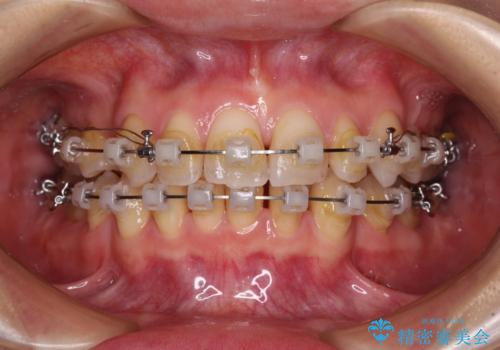

- クリアブラケット

骨格的な左右差と、歯列から外れている歯が上下で左右非対称になっていることから、上下正中が歯1本分ずれている状態でした。

八重歯の改善と、上下の正中位置を極力合わせていくことを目的として、上下左右の第一小臼歯4本を抜歯し、ワイヤー装置にて矯正治療を行うこととしました。

アンカースクリューを用いて正中位置を調整したことで、上下の正中位置をほぼ一致させることができました。